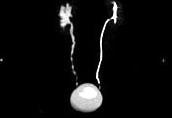

问题 男,47岁,腰痛、腰胀2个月余伴低热、乏力,如影像资料所示,下列哪项说法正确 ( )

选项 A、考虑为右输尿管占位病变 B、考虑为右输尿管结核 C、右侧输尿管多发性生理性狭窄 D、右侧肾盂轻度积水 E、右侧输尿管多发性狭窄,呈“串珠样”改变

答案 BDE